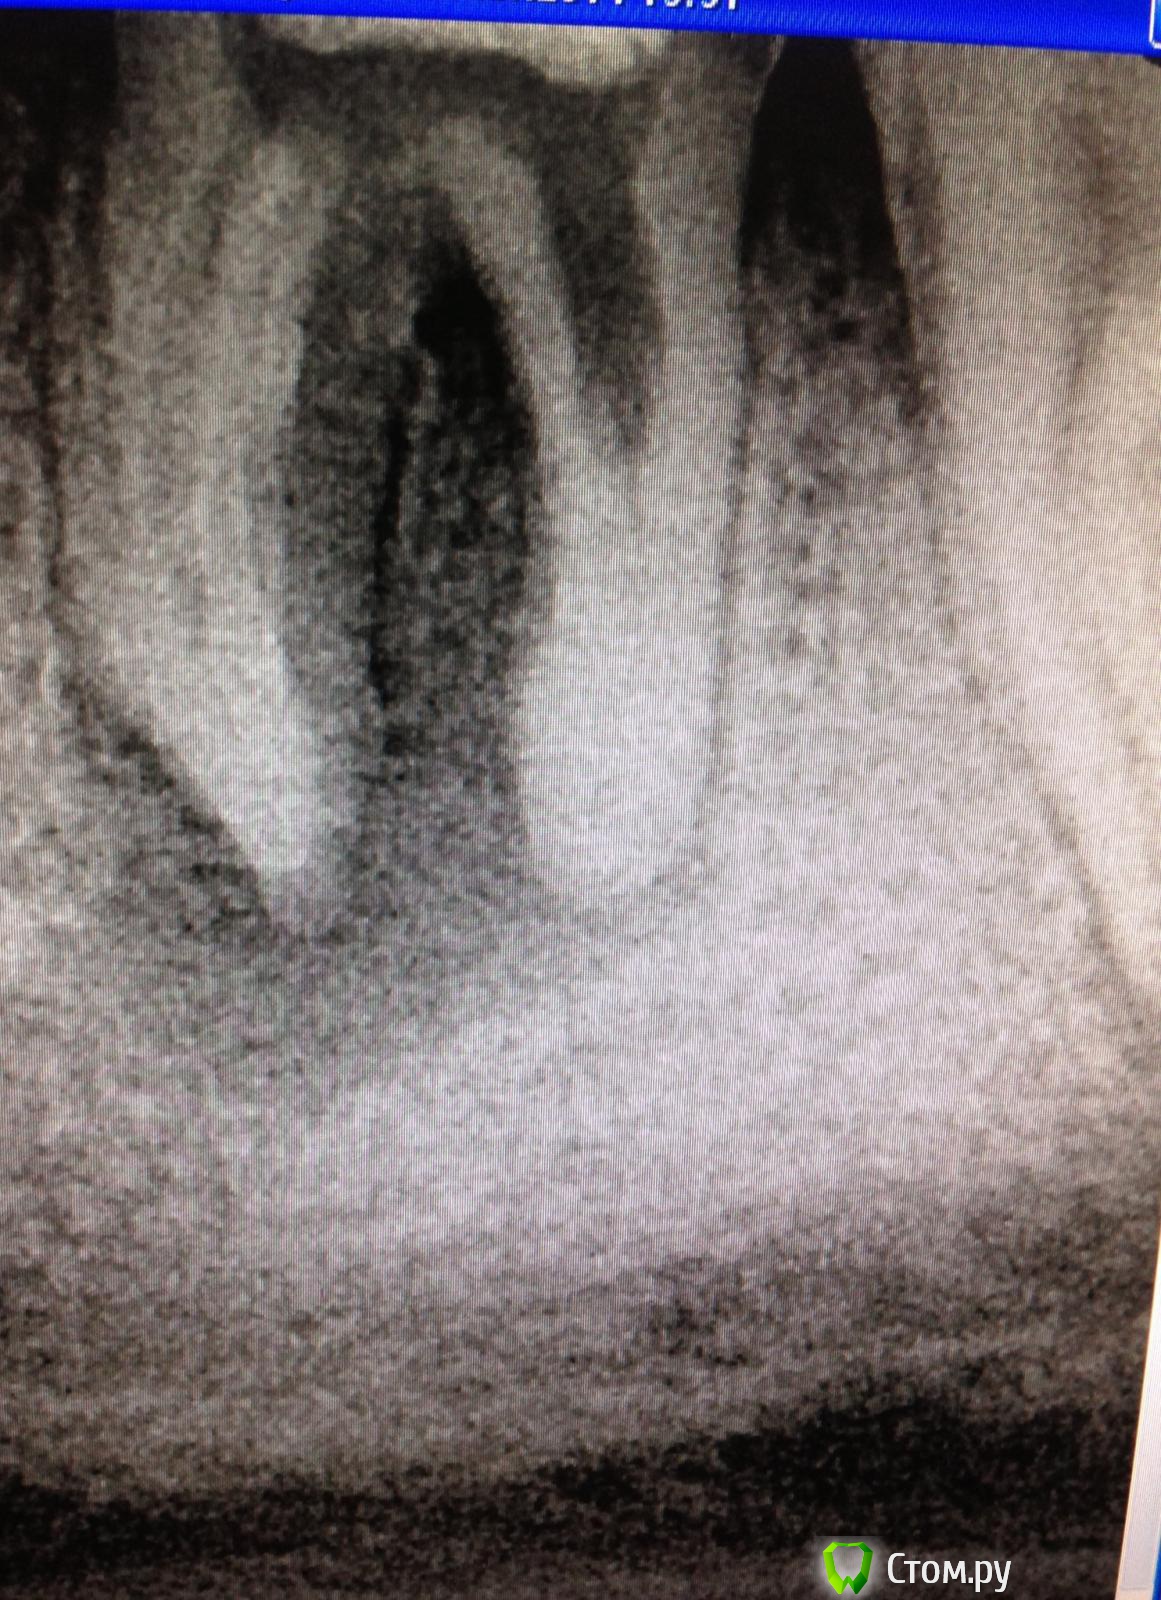

SSTi Опубликовано 29 мая, 2014 Автор Поделиться Опубликовано 29 мая, 2014 Из серии: не знаю зачем, но надо...Бессимптомный 47. Поступил приказ сверху - сделать эндо. Делаем. Коронка медиально разрушена на уровне с десной. Пациент ооочень слюнявый. С горем пополам соорудил стенку, чтобы одеть коффер. Одел- выдохнул. Нашел все устья, в медиальные заходила только 10ка. В дистальный 15ка. Везде склероз жуткий. Кое-как прошел все каналы ручными до 25. Pathfile , protaper до s2. Дальше побоялся. Все очень узко и хрустит. Мылся, мылся. Мылся. Гипохлор, эдта и хлоргексидин. Медиальные сходятся в средней трети. Запаковал сначала язычный. Снимки не очень( с рентген аппаратом проблема кое-какая). Но что есть , то есть. С коффером не делал снимки( держался еле еле), как запломбировал- времянка и бегом на снимок. Ссылка на комментарий

faity Опубликовано 29 мая, 2014 Поделиться Опубликовано 29 мая, 2014 артефакт на снимке или перелом или дельта? Ссылка на комментарий

SSTi Опубликовано 29 мая, 2014 Автор Поделиться Опубликовано 29 мая, 2014 Сильно увеличивал контрастность, чтобы можно было разглядеть что-нибудь. В латераль затекло бы, не думаю , что перелом. Сделаю еще один снимок в следующий раз. Я даже не заметил. Спасибо, что нашли)) Ссылка на комментарий